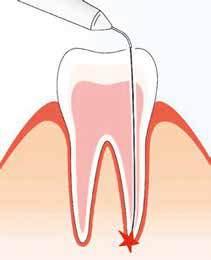

Il successo del trattamento endodontico è strettamente influenzato da due fattori: l’anatomia endodontica e la persistenza di batteri nei canali dopo il trattamento.

Quando si parla di canale radicolare, in realtà, occorre pensare ad un sistema anatomico complesso che, insieme ai canali principali, può presentare canali laterali che dipartono dal canale principale, canali accessori che nella porzione apicale concorrono alla formazione del delta, ed infine gli istmi, comunicazioni nastriformi strette tra due canali radicolari. Di fronte a tali complessità anatomiche, è impossibile pensare che anche eseguendo una buona sagomatura, con l’impiego dei migliori materiali e tecniche attualmente a disposizione, si possano raggiungere e trattare tutti i canali per rimuovere meccanicamente la dentina infetta ed i tessuti necrotici presenti all’interno di essi.

La letteratura dimostra che almeno il 35% della superficie canalare non viene toccata dagli strumenti durante la fase di sagomatura, indipendentemente dalla tecnica utilizzata. Queste superfici non toccate sono composte da tessuti colonizzati da microorganismi potenzialmente infetti, batteri e le loro tossine, che rappresentano un pericolo di re-infezione dello spazio endodontico e conseguente fallimento della terapia. Per questo motivo, la detersione e disinfezione dei canali rappresenta una fase indispensabile per ridurre la carica batterica presente all’interno di essi. La sopravvivenza dei batteri può indurre e sostenere l’infiammazione dei tessuti peri-radicolari e la potenziale insorgenza di recidive.

Dato però che la totale eliminazione dei batteri non è una condizione assicurabile (per questo motivo si parla di disinfezione e non di sterilizzazione), la carica batterica ancora presente verrà isolata all’interno degli spazi non trattati attraverso l’otturazione tridimensionale dei canali, impedendo la loro proliferazione.